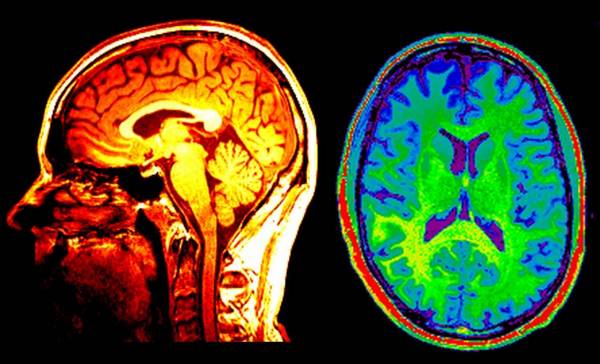

Необходимо сделать следующие обследования:

- проверка активности мозга и состояния сосудов;

- МРТ внутренних органов.